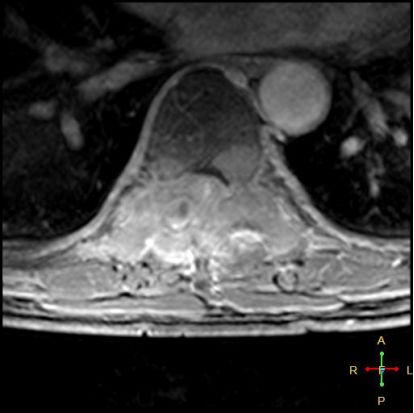

——恶性压缩性骨折MR信号特点—— 由于肿瘤组织的侵犯,T1WI上椎体呈弥漫性低信号,T2WI呈高信号,增强扫描呈明显不均匀强化。

转移瘤 椎弓根改变:椎弓根膨大仅见于恶性压缩性骨折,故为其特异性,可作为鉴别诊断的依据。

椎旁软组织肿块:在转移瘤中,受累椎体周围多出现分叶状或肿瘤样软组织肿块,此征象仅见于恶性压缩性骨折。故,椎旁薄环状软组织与瘤样软组织肿块是鉴别骨折性质较有特征性的征象。